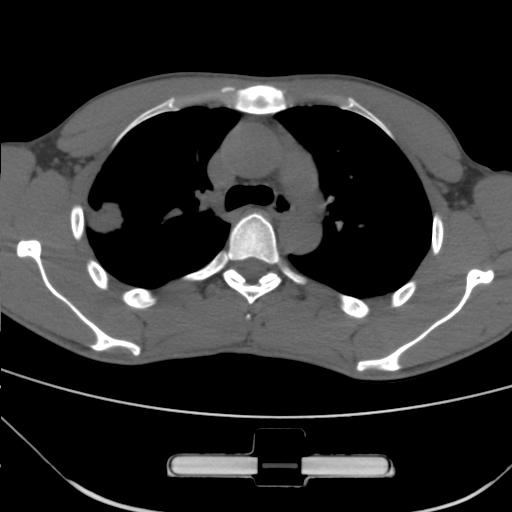

标题: CT25483:肺部病变 请指教

车祸伤者

右肺上叶后段近胸膜下结节样异常密度灶,似见分页及毛刺,考虑右肺上叶周围型肺ca,建议穿刺病理检查

周围型肺ca与炎性假瘤待鉴别。建议穿刺病理检查

缺乏病史,症状体征,但这个孤立结节具备了几乎所有的恶性征象:分叶,毛刺,空泡征,胸膜凹陷征,血管集束。